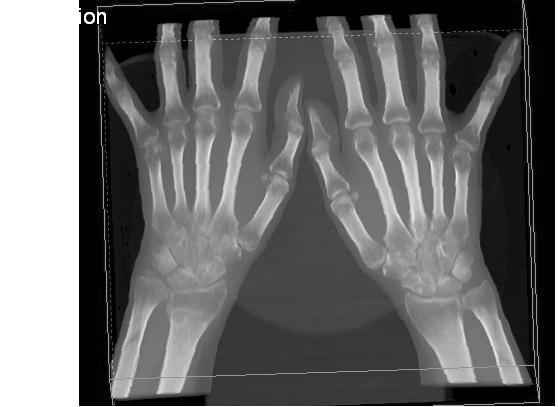

Дальнейшее лечение консервативное. Через 6 недель- гипс снят, назначено ЛФК. Пациентка крайне недовольна. Говорит, что на снимке у нее выступает кость, я ей сломал руку и.т.д. В общем началось. Пациентка прочитала в интернете наверное все, что есть по данной травме. По заключениями рентгенологов и консультанта из КДЦ областной больницы - стояние отломков допустимое. Объективно говоря- снижена высота лучевой кости, диастаз лучелоктевого сочленения, и не сросся шиловидный отросток. однако на РКТ при сравнении с другой стороной- разница незначительная.

1.Прошу объективно оценить качество нашей репозиции на момент 21.12. (неужели так плохо?). Что на снимках при снятии гипса- сам вижу.

2. сравнить снимки РКТ (с двух сторон)- так ли велико укорочение лучевой кости и лучелоктевой диастаз.